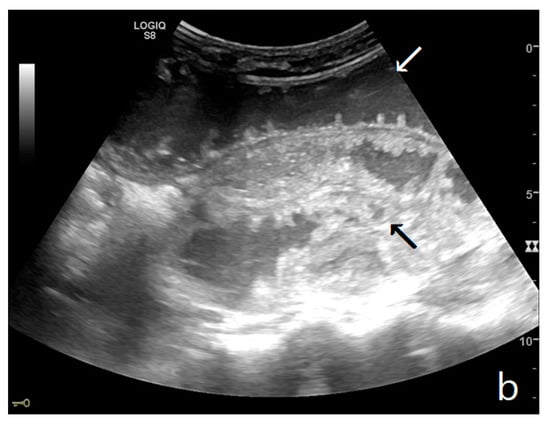

Figure 3.

A decompensated SBO, presenting fluid-filled, dilated small bowel loops with increased parietal thickening (*) (a) and free fluid between bowel loops (a). ‘Caliber jump’: a difference in caliber between the swollen loops upstream (white arrows) (a,b) and the collapsed loops downstream of the obstruction (black arrows) (a,b).

The persistence of obstruction causes an increase in endoluminal pressure, and the liquid content normally present in the intestinal lumen cannot be reabsorbed. Bowel layers act as a sponge, determining the passage of fluid in the peritoneal cavity (Figure 3a,b). In the initial phase, the liquid is disposed between the recesses of the mesenteric fan, giving rise to the characteristic ‘sign of the thong’ [39]. With the persistence of the obstruction, the amount of free fluid increases, and it can be found in the abdominal cavity. The presence of free fluid is directly correlated to bowel parietal vascular alterations [13,37,40,41].